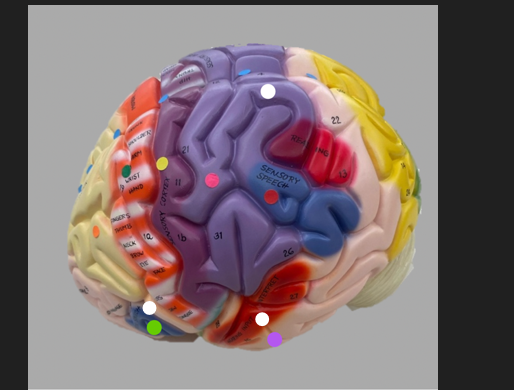

orange dot

frontal lobe

blue dot

longitudinal fissure

dark green dot

precentral gyrus

pink dot

postcentral gyrus

yellow dot

central sulcus

white dot

parietal lobe

light green dot

Broca’s Area

red dot

Wernicke’s Area

orange dot

occipital lobe

blue dot

parieto-occipital sulcus